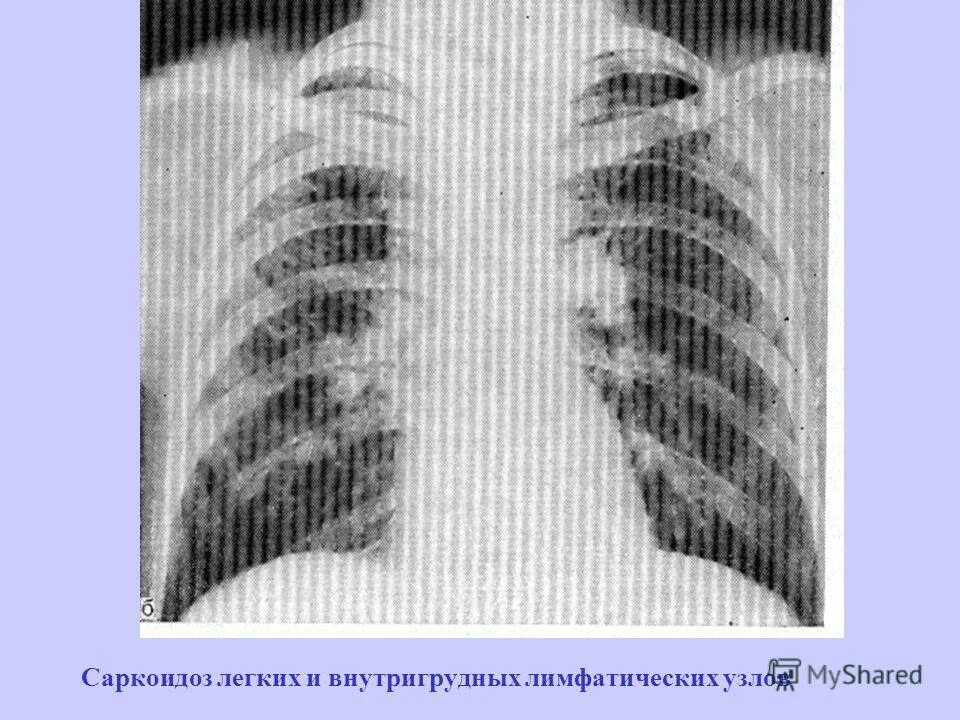

Увеличение внутригрудных лимфатических узлов